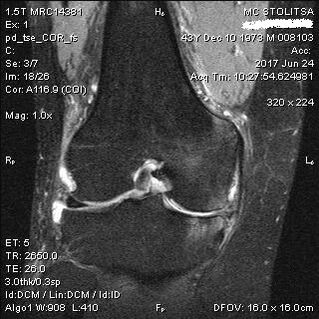

Diagnostika a liečba artrózy kolenného kĺbu

Diagnostika artrózy kolenného kĺbu prebieha v ordinácii reumatológa alebo ortopéda. Lekár skúma postihnutý kĺb, prehmatáva ho, počúva sťažnosti a kladie ďalšie otázky. Vykonáva niekoľko testov - napríklad požiada pacienta, aby ohýbal nohu alebo prešiel niekoľko krokov. Potom, ak je potrebné objasniť štádium ochorenia alebo povahu patologických zmien, pošle vás na ďalšie štúdie. Napríklad pre počítačovú tomografiu alebo rádiografiu.